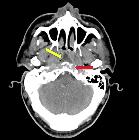

Osteomyelitis im Clivus

CT

CT is superior to both MRI and plain film in depicting the bony margins and identifying a sequestrum or involucrum. The CT features are otherwise similar to plain films. The overall sensitivity and specificity of CT is low, even in the setting of chronic osteomyelitis, and according to one study are 67% and 50%, respectively .